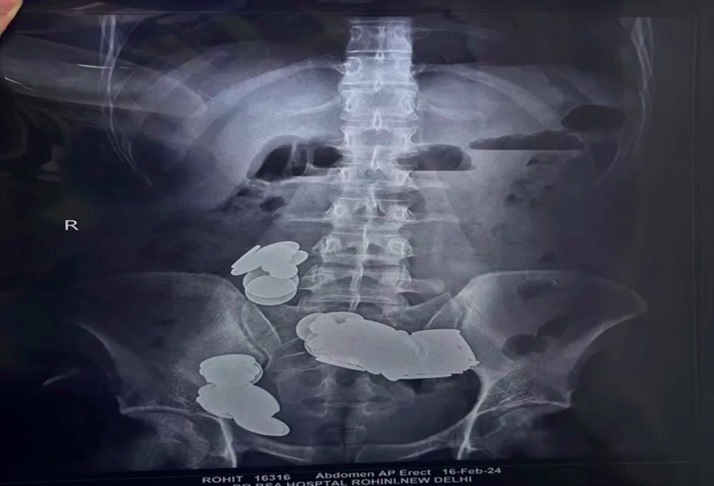

À beira da morte: Homem engole 39 moedas e 37 ímãs